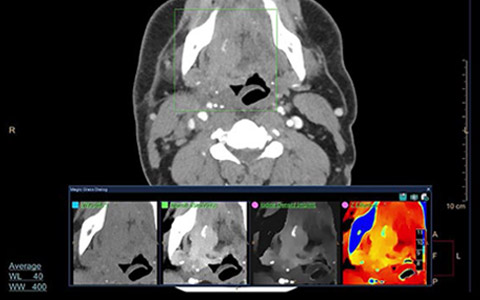

Zobacz, jak współpraca firm Philips i CARTI przynosi korzyści pacjentom wymagającym skomplikowanego leczenia i jak tomograf IQon Spectral CT zmienił jego przebieg*.